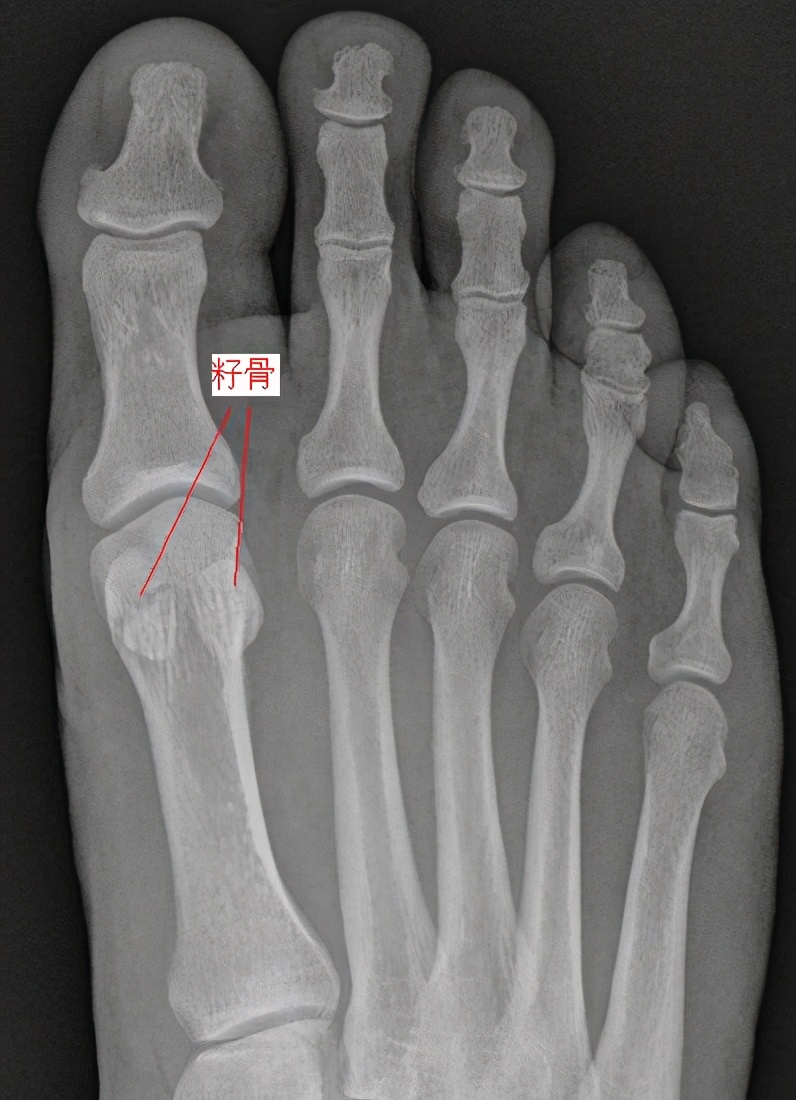

草地趾的主要症状是大拇指与脚掌相连部位附近的局部疼痛、肿胀、淤斑和肌紧张,在行走时出现疼痛步态(无意识地避免大拇趾负重)。可通过核磁共振等影像学方面的检查来确定关节囊附近的软组织损伤,并排除籽骨、关节面、跖骨、腱鞘等其他类型的病变和损伤。如果只是单纯的第一跖趾关节软组织扭伤(草地趾),则可在急性症状期采用休息、冰敷、加压包扎、抬高患肢的手段缓解疼痛和肿胀,当急性症状得控制后,可在保护装置(例如:行走靴、硬底鞋、拇趾人字绷带)的辅助下逐步恢复到日常活动和体育活动。但如果是其他疾病引发的症状,则要根据情况考虑实施不同的治疗方案。介于此,应将草地趾与下列症状相近的疾病进行区分。

1、拇趾骨折、脱位。可通过影像学证据加以排查(例如:通过X光线、骨扫描、CT、MRI等手段找到显著证据)。2、拇趾僵硬、跖趾关节炎。多与骨刺、骨赘、组织纤维化等慢性病变有关,一般都不是急性疾症;可通过影像学证据加以排查。3、籽骨损伤。压痛点更加集中于籽骨,范围更小。可通过影像学证据加以排查。4、籽骨疲劳骨折。压痛点更加集中于籽骨,范围更小;慢性疾症;可通过影像学证据加以排查。5、二分籽骨。籽骨因先天未融合而出现裂痕,影像学检查可见籽骨中间的低密度线(非骨折线);无压痛;双侧同时发生的概率较大。6、籽骨关节炎。压痛点更加集中于籽骨,范围更小;活动时疼痛加重;可通过影像学证据加以排查。

7、籽骨缺血性坏死。压痛点更加集中于籽骨,范围更小;影像学检查可见附近游离体。8、屈肌腱狭窄性腱鞘炎。可见“扳机现象”(屈伸拇趾时有弹响或顿挫);拇(足)长屈肌腱活动时疼痛,核磁检查可见腱鞘炎。9、痛风。可见跖趾关节的压痛、红斑,疼痛前无急性损伤经历,尿酸高,关节穿刺可见尿酸盐结晶。